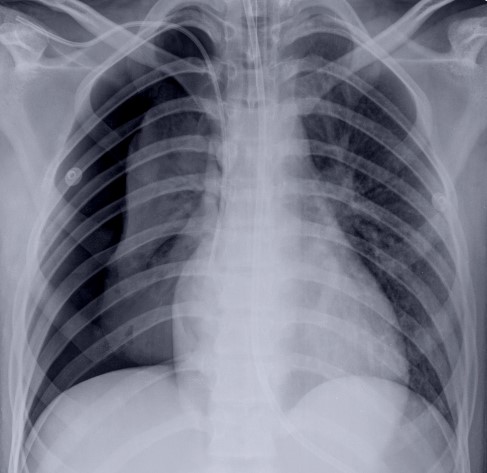

O Pneumotórax consiste em ar na cavidade pleural, acarretando colapso pulmonar parcial ou completo. Na clínica, os sintomas são falta de ar e dor quando respira.

Os principais sinais de pneumotórax na radiografia são:

1. Hipertransparência sem vasos e brônquios;

2. Colabamento do pulmão homolateral;

3. Delimitação da pleura visceral;

4. Mais bem visto na radiografia em expiração;

5. Desvio do mediastino contra lateral e herniação pulmonar, indicando pneumotórax hipertensivo.